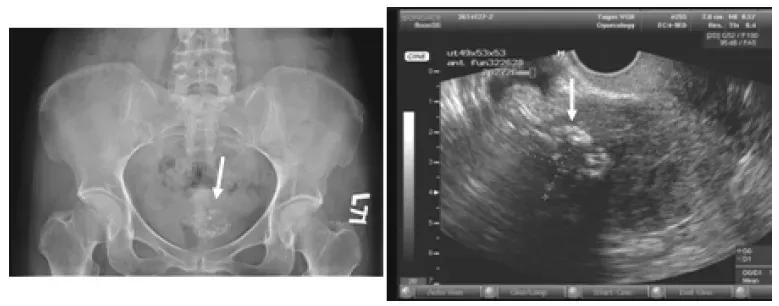

【113-2 醫學(六) 第73題】45歲女性病人到醫院做健康檢查,腹部X光片顯示骨盆腔病變如圖示;進一步進行經陰道超音波檢查,結果發現異常如圖示。最可能的診斷為何?